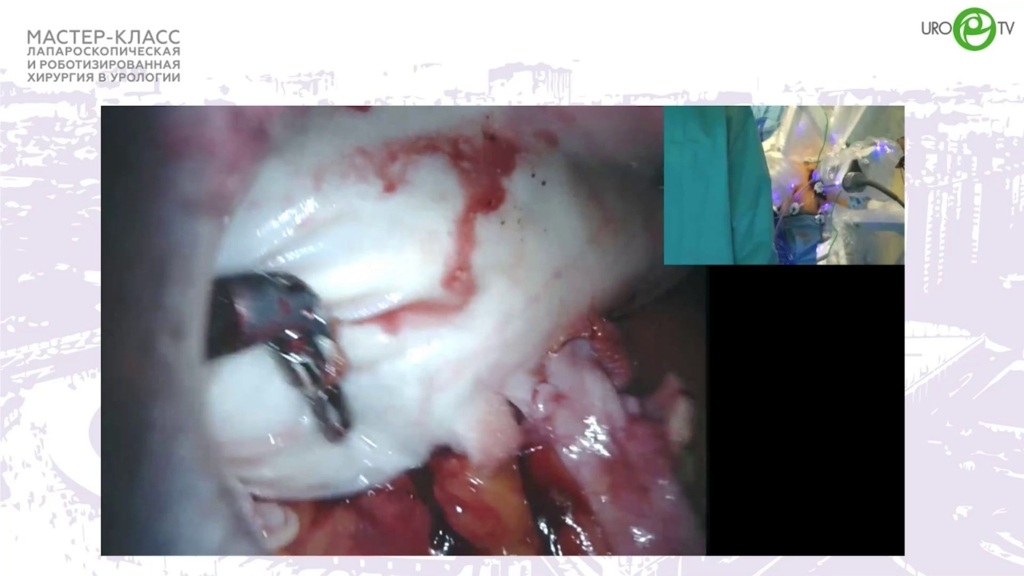

Медведев В.Л. - Робот-ассистированная чрескожная адэномэктомия